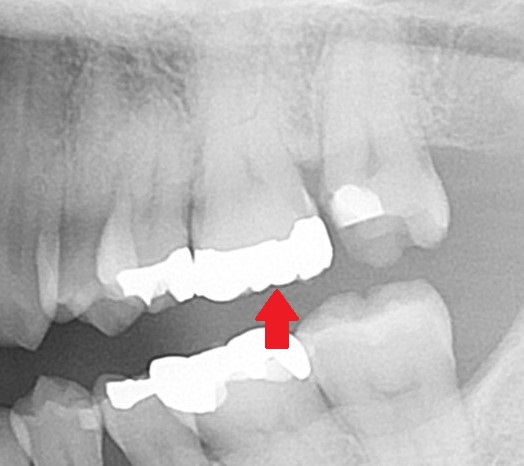

こちらの大きい銀歯の中に虫歯が広がっています。

まずはレントゲンを見てみましょう。

赤い矢印の歯が写真の銀歯の歯です。

この歯に虫歯があるのでしょうか?

正直、私でもレントゲン写真から虫歯がどのくらい広がっているか分かりません。

虫歯があるように見えないかもしれません。